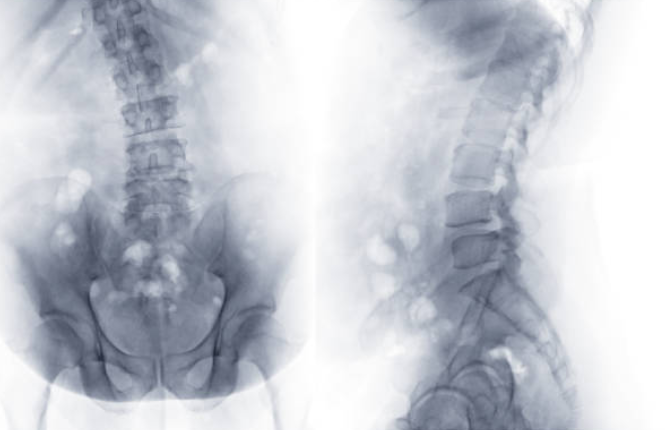

척추측만증

허리통증의 원인 중 척추측만증이 있습니다. 척추는 정면에서 보았을 때 일자로 곧게 뻗어야 정상이지만, 옆으로 구부러지면 척추측만증이라고 합니다. 등 부위에 뒤로 나온 굴곡이 지나치게 심해지면 꼽추라고 표현하는 척추기형이 발생합니다. 척추가 굽는 것을 척추측만증이라고 합니다.